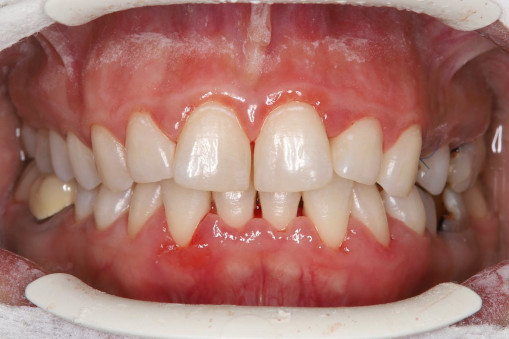

А прежде, чем вы посмотрите фотографии «до» и «после» лечения слизистой оболочки полости рта, проведенных в нашей клинике, хочу поблагодарить большое количество наших пациентов, которые поверили, прониклись нашей концепцией, и мы вместе, именно вместе победили болезни десны, гингивит и пародонтит!

До/после лечения